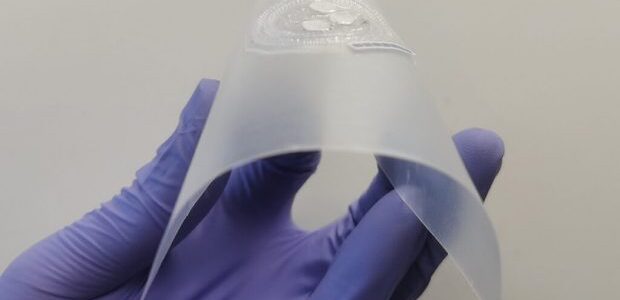

Μήπως πάσχετε από διαβήτη, καρδιοπάθεια, νεφροπάθεια ή ουρική αρθρίτιδα και δεν το γνωρίζετε; Ενα φορετό μόνιτορ μπορεί να το διαγνώσει στον ιδρώτα σας ενώ γυμνάζεστε, μετρώντας τα επίπεδα σημαντικών βιοδεικτών. Το νέο μόνιτορ που… φοριέται στο μπράτσο αποτελεί προϊόν τρισδιάστατης εκτύπωσης και αναμένεται στο μέλλον να προσφέρει έναν απλό, μη επεμβατικό τρόπο διάγνωσης κοινών νόσων. Αυτό αναφέρουν οι δημιουργοί του από το Πολιτειακό Πανεπιστήμιο της Ουάσινγκτον (WSU) με δημοσίευσή τους στο επιστημονικό περιοδικό «ACS Sensors».

Για τη δημιουργία του πρωτοτύπου τους οι ερευνητές χρησιμοποίησαν τρισδιάστατη εκτύπωση καθώς και μια απλή διαδικασία κατασκευής που περιελάμβανε ένα μόνο στάδιο. Συγκεκριμένα χρησιμοποίησαν έναν μονοατομικό καταλύτη και ενζυμικές αντιδράσεις ώστε να ενισχύσουν το σήμα και να μπορούν να μετρούν χαμηλά επίπεδα βιοδεικτών. Τρεις βιοαισθητήρες που φέρει η συσκευή αλλάζουν χρώμα ώστε να δείξουν τα επίπεδα συγκεκριμένων βιοδεικτών.

Το νέο μόνιτορ μετρά τον ιδρώτα στο μπράτσο ενός εθελοντή. Στο πλαίσιο δοκιμής του πρωτοτύπου της συσκευής ο ιδρώτας βάφτηκε με κόκκινο χρώμα. Το μπλε επίθεμα που παρουσιάζεται επίσης στην εικόνα χρησιμοποιήθηκε για εργαστηριακή σύγκριση (Washington State University)

Ωστόσο η ποσότητα των βιοδεικτών στον ιδρώτα είναι πάρα πολύ μικρή και δύσκολο να μετρηθεί. Παρότι υπάρχουν και άλλες συσκευές ανίχνευσης προβλημάτων υγείας στον ιδρώτα, μέχρι σήμερα αυτές είναι πολύπλοκες και απαιτείται ειδικός εξοπλισμός για την κατασκευή τους. Παράλληλα για να είναι αυτού του τύπου οι αισθητήρες χρηστικοί χρειάζεται να είναι εύκαμπτοι.

Η καινοτομία της νέας συσκευής

Η νέα φορετή συσκευή φαίνεται να λύνει τα προβλήματα των προκατόχων της. «Είναι καινοτόμο να χρησιμοποιούνται μονο-ατομικοί καταλύτες οι οποίοι ενισχύουν την ευαισθησία και την ακρίβεια του μόνιτορ της υγείας» ανέφερε η Ανι Ντου, καθηγήτρια στη Σχολή Μηχανολόγων Μηχανικών και Μηχανικής Υλικών του WSU η οποία ηγήθηκε της έρευνας μαζί με τον καθηγητή Κιου.

Ο φορητός και… φορετός καταγραφέας της υγείας που ανέπτυξαν οι επιστήμονες του WSU αποτελείται από μικροσκοπικά κανάλια τα οποία μετρούν τη ροή του ιδρώτα καθώς και τη συγκέντρωση των βιοδεικτών. Καθώς τα κανάλια αυτά κατασκευάζονται με χρήση τρισδιάστατου εκτυπωτή, δεν απαιτούν τη χρήση κάποιας υποστηρικτικής δομής η οποία θα μπορούσε να προκαλέσει θέματα μόλυνσης κατά την αφαίρεσή τους, τόνισε ο δρ Κιου.

Η συσκευή τοποθετείται στο μπράτσο του εθελοντή και μετρά τους βιοδείκτες στον ιδρώτα που εκείνος εκκρίνει. Μάλιστα στο πλαίσιο δοκιμής του πρωτοτύπου, ο ιδρώτας βάφτηκε με κόκκινο χρώμα. Χρησιμοποιήθηκε επίσης ένα μπλε επίθεμα για εργαστηριακή σύγκριση.